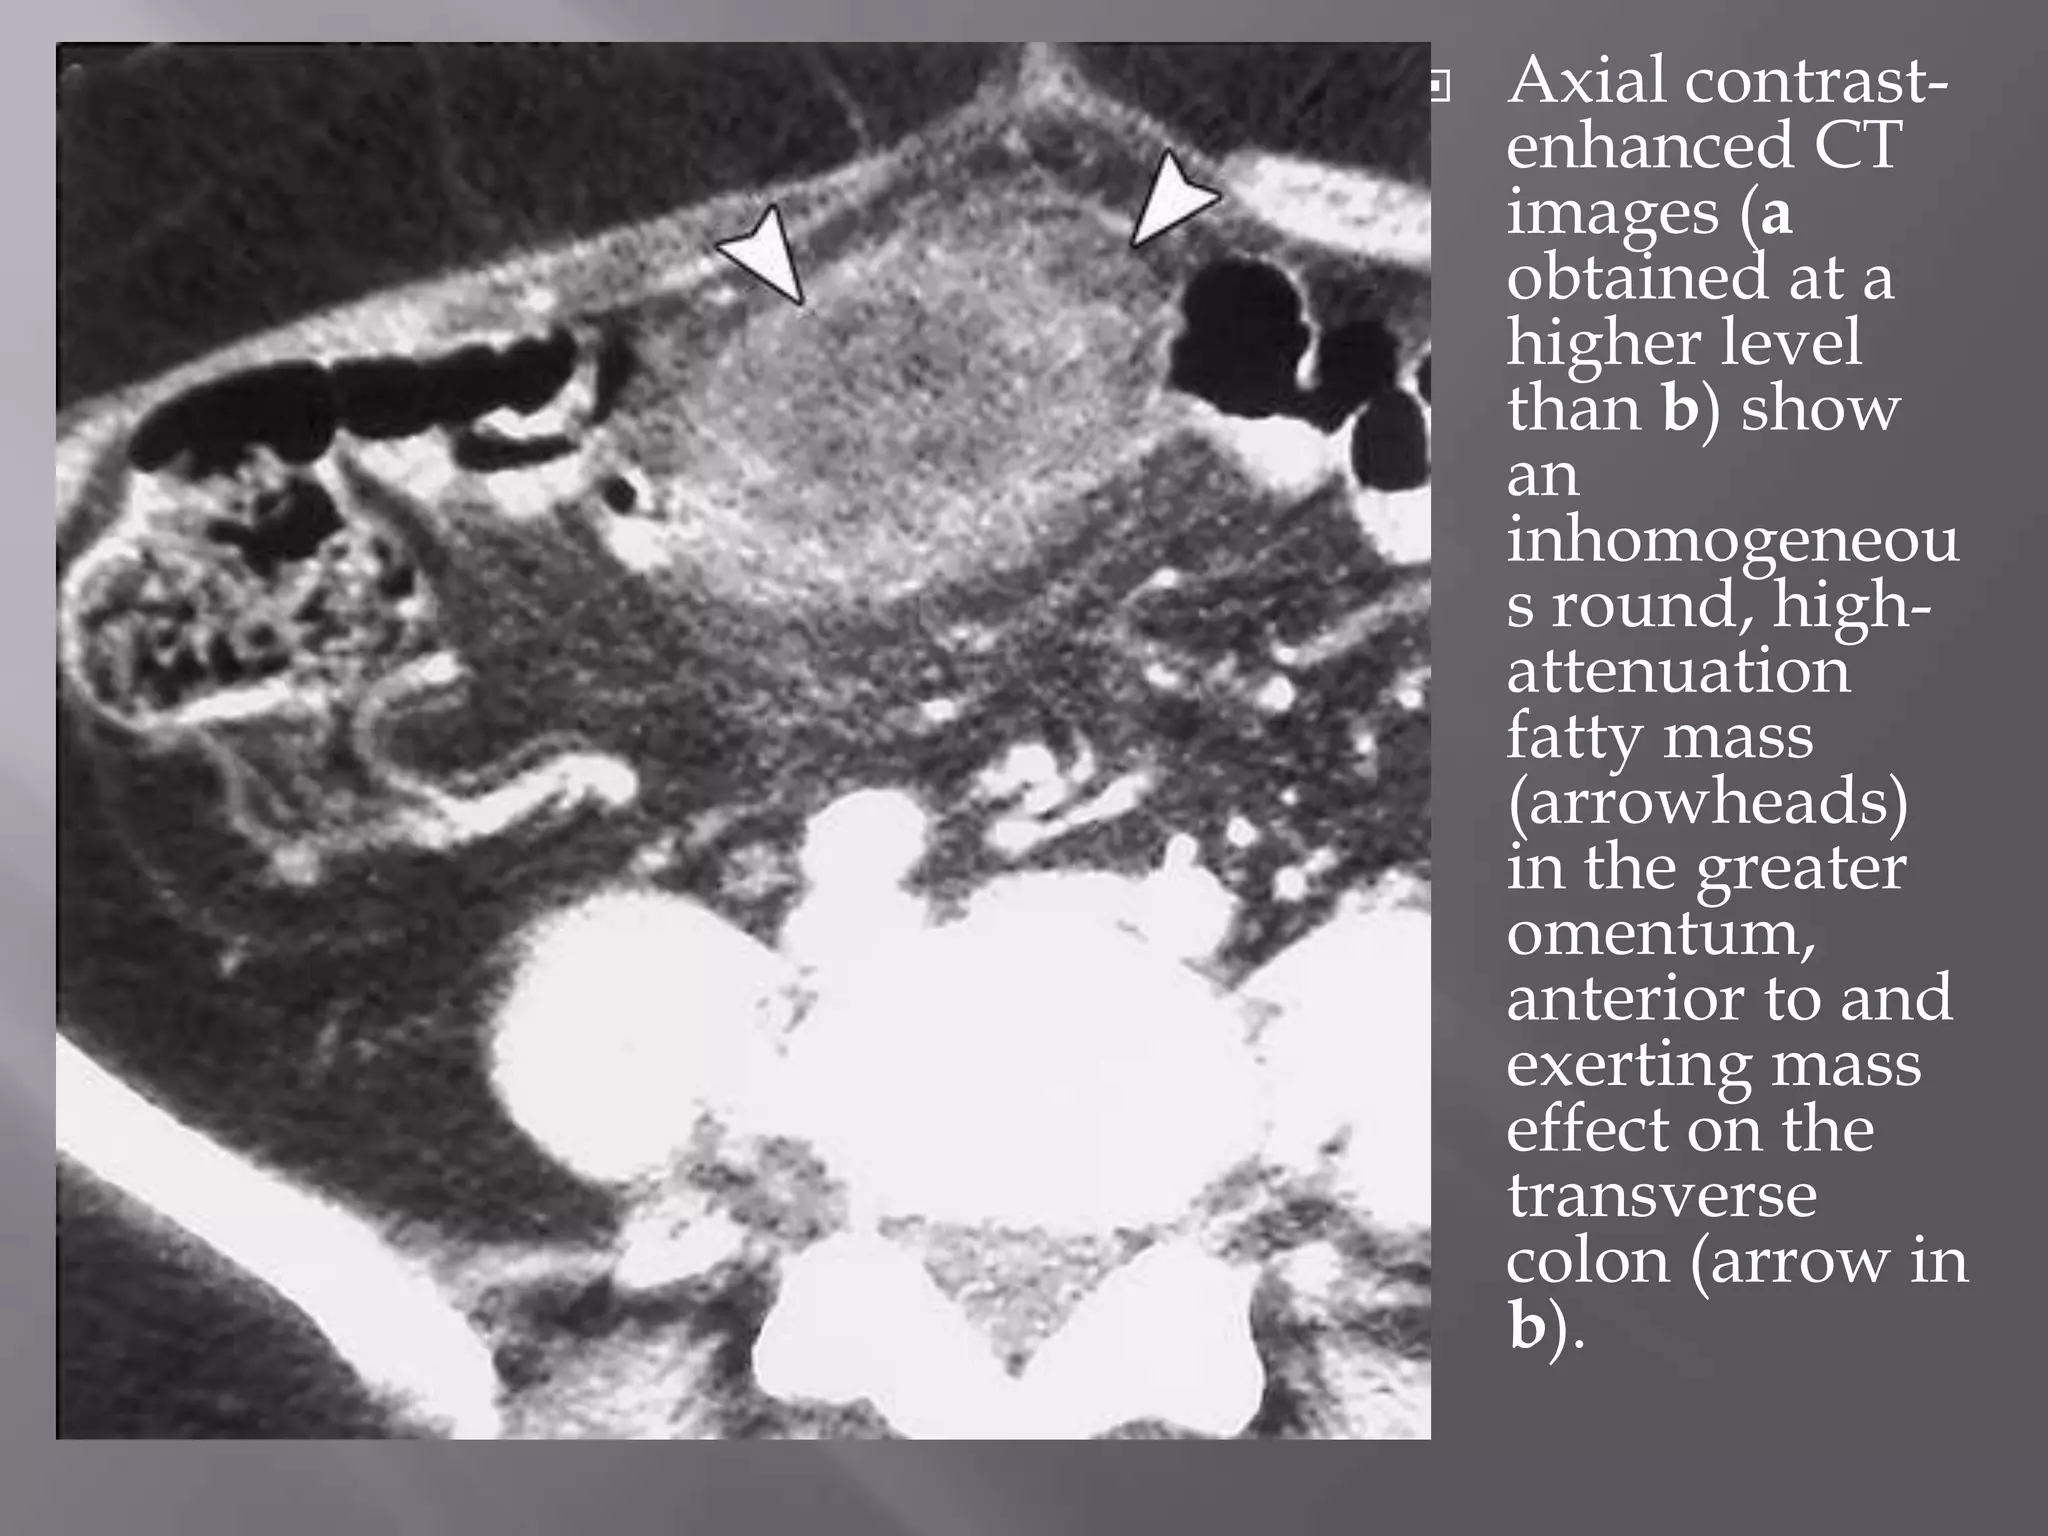

 Axial contrast-

enhanced CT

images (a

obtained at a

higher level

than b) show

an

inhomogeneou

s round, high-

attenuation

fatty mass

(arrowheads)

in the greater

omentum,

anterior to and

exerting mass

effect on the

transverse

colon (arrow in

b).

 Axial contrast- enhancedCT images (a obtained at a higher level than b) show an inhomogeneou s round, high- attenuation fatty mass (arrowheads) in the greater omentum, anterior to and exerting mass effect on the transverse colon (arrow in b).